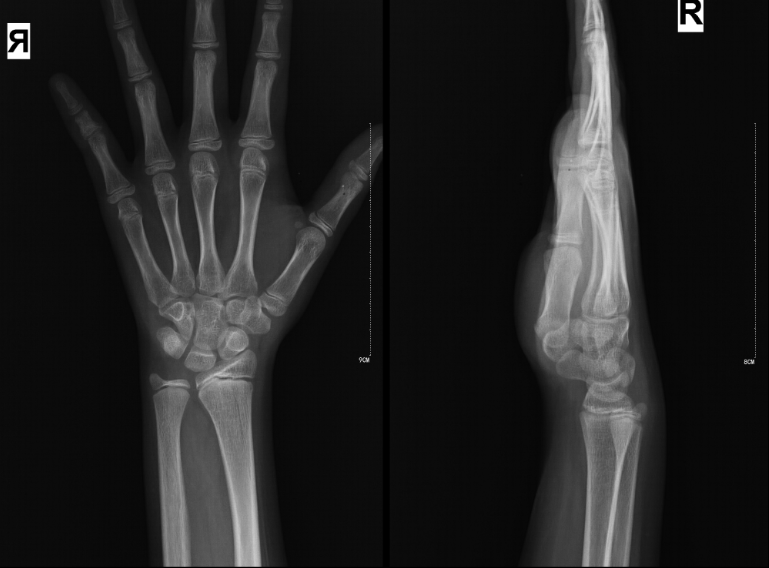

DR影像图

方案介绍

DR影像图具有以下特点:

高分辨率:DR技术相比传统X线摄影具有更高的分辨率,能够更清晰地显示肺部细微结构。

数字化成像:图像以数字形式存储和传输,便于保存、打印和远程会诊。

动态范围宽:能够同时显示高密度和低密度的组织,如骨骼和肺部。

后处理功能强大:可对图像进行增强、放大、缩小等处理,提高诊断准确性。